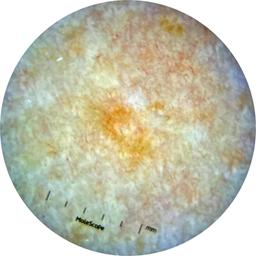

ISIC_9097190

Information

Dimensions

2049 x 2049

Attribute to

MEL-SELF Trial, https://www.sydney.edu.au/medicine-health/our-research/research-centres/melself-project.html

License

Clinical

Field Value

acquisition_day 181

age_approx 45

anatom_site_1 Trunk

anatom_site_2 Anterior trunk

anatom_site_general anterior torso

diagnosis_1 Benign

family_hx_mm False

fitzpatrick_skin_type I

image_manipulation instrument only

image_type dermoscopic

lesion_id IL_9115938

patient_id IP_3026018

personal_hx_mm True

sex female